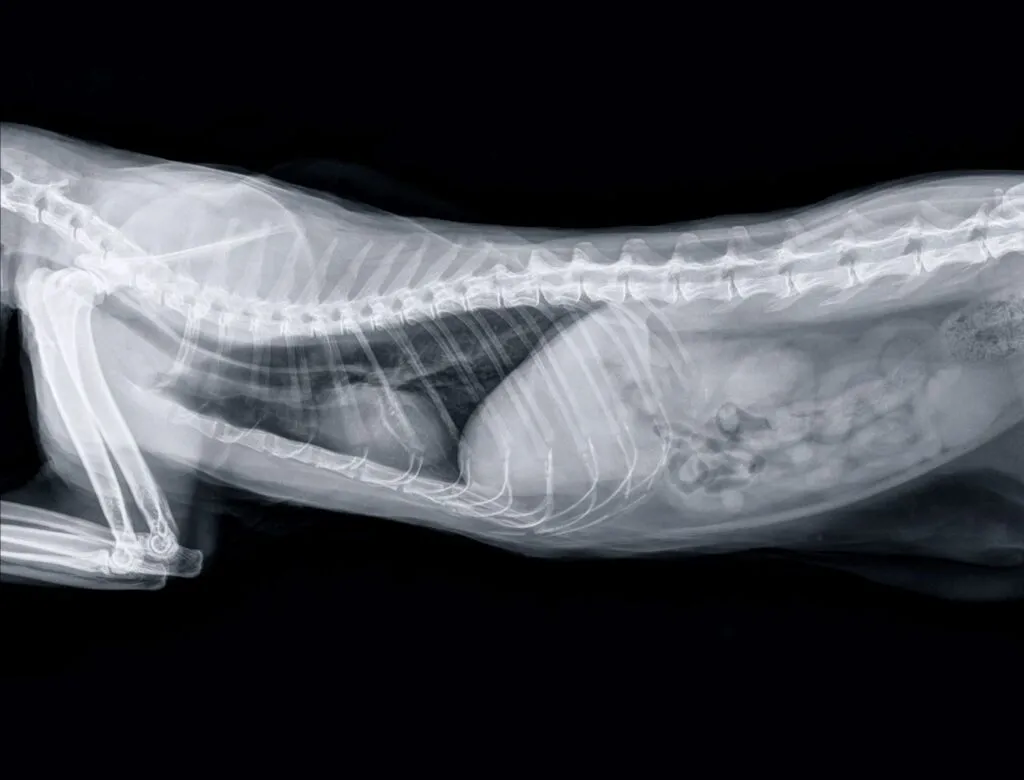

Si l’état général du chat est déjà affecté, des examens supplémentaires peuvent être réalisés, comme une radiographie ou une échographie. Une analyse sanguine peut également être demandée pour évaluer l’équilibre hydrique et électrolytique du chat, et pour détecter une éventuelle maladie sous-jacente.

© Stefano Garau / stock.adobe.com